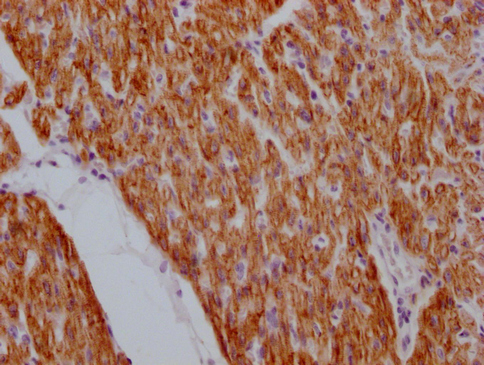

IHC image of CSB-MA923561 diluted at 1:100 and staining in paraffin-embedded human heart tissue performed on a Leica BondTM system. After dewaxing and hydration, antigen retrieval was mediated by high pressure in a citrate buffer (pH 6.0). Section was blocked with 10% normal goat serum 30min at RT. Then primary antibody (1% BSA) was incubated at 4°C overnight. The primary is detected by a Goat anti-mouse IgG polymer labeled by HRP and visualized using 0.05% DAB.

Application Recommended Dilution IHC 1:20-1:200 -